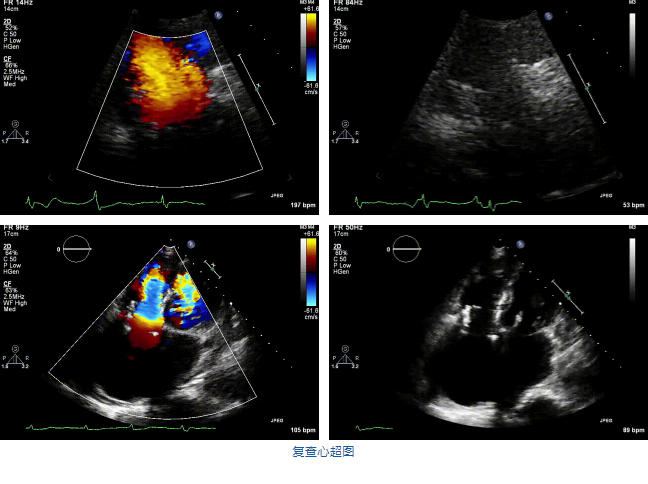

2021年12月7日,復旦大學附屬中山醫(yī)院葛均波院士團隊完成的首批兩例LuX-Valve Plus經(jīng)血管三尖瓣置換患者順利出院,從患者入院至出院僅歷時一周時間,出院時患者狀態(tài)恢復良好,復查心超三尖瓣無反流。

兩例患者是都是外科手術(shù)高危的極重度三尖瓣反流的老年女性,反復下肢水腫、腹脹、納差,活動耐力減退。一例患者風濕性心臟病,二尖瓣生物瓣置換術(shù)后,房顫,心超顯示三尖瓣極重度反流(最大反流寬度15mm);另一例患者房顫,心超示三尖瓣極重度反流(最大反流寬度23mm)。

結(jié)合術(shù)前CT評估結(jié)果,葛均波院士團隊最終決定選用LuX-Valve Plus 50mm和55mm兩種型號的瓣膜,并于2021年11月30日順利完成LuX-Valve Plus經(jīng)血管三尖瓣置換術(shù),手術(shù)室即刻拔除氣管插管,術(shù)后第二天轉(zhuǎn)出心內(nèi)科監(jiān)護室,下床活動。術(shù)后患者三尖瓣反流癥狀得到顯著改善,復查心超結(jié)果顯示人工三尖瓣瓣膜支架固定穩(wěn)定,瓣葉關(guān)閉形態(tài)未見異常,未見明顯反流。